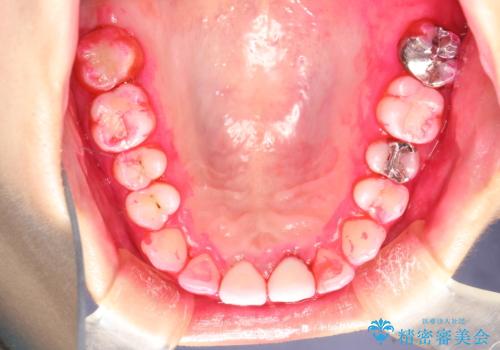

開始前

かなり久しぶりの歯科医院との事で、全体的に古くからの歯垢・歯石が多く付着していたため、自費クリーニング(PMTC)60分コース・歯周ポケット検査(保険適応)を行いました。